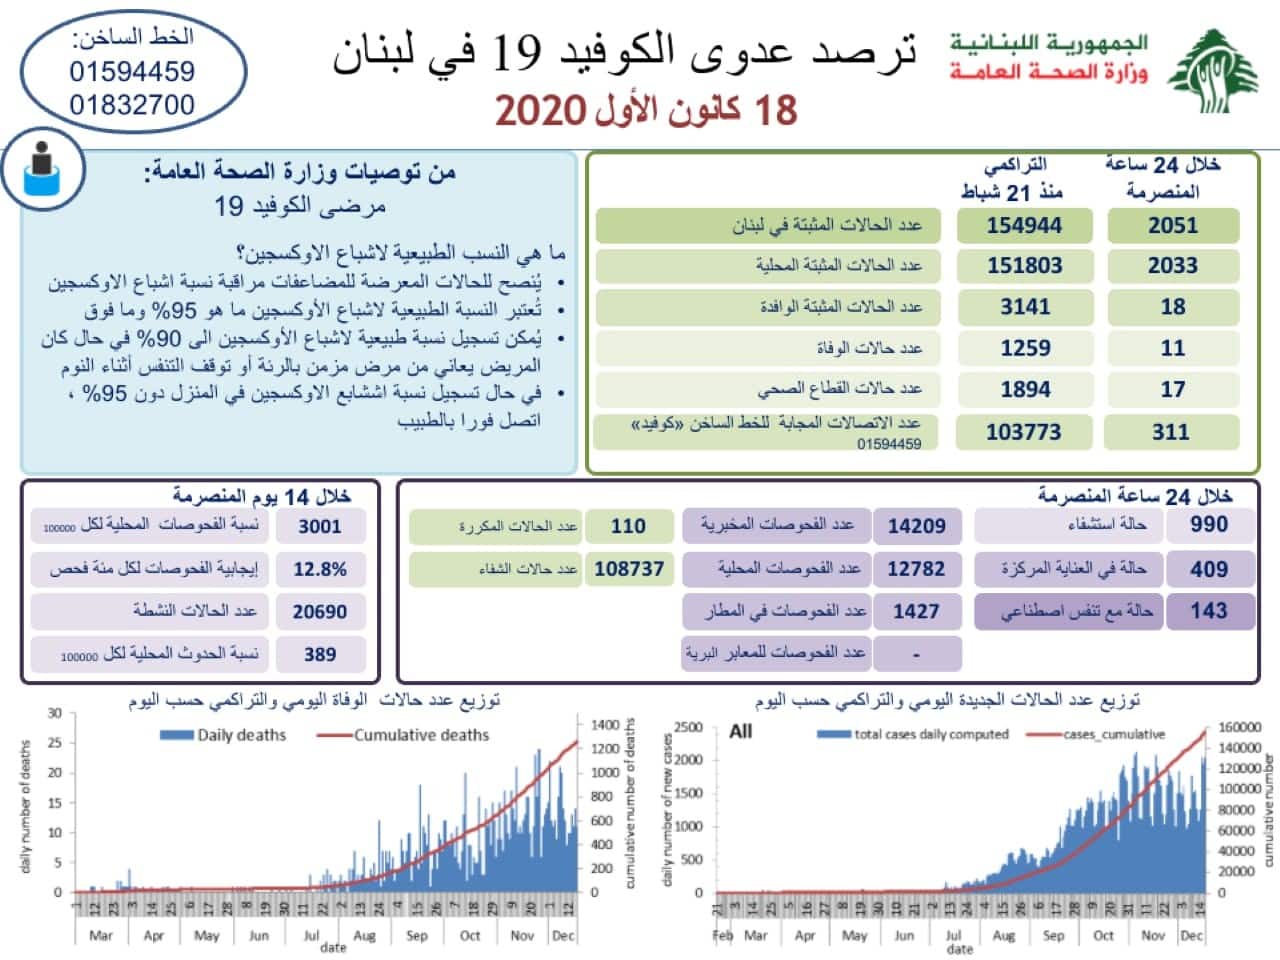

Liban/Coronavirus: 2051 cas et 11 décès ce vendredi

Le nombre de nouveaux cas est repassé au-dessus du seuil des 2000 personnes, indique le ministère de la santé. Ainsi, on dénombre 2051 personnes...